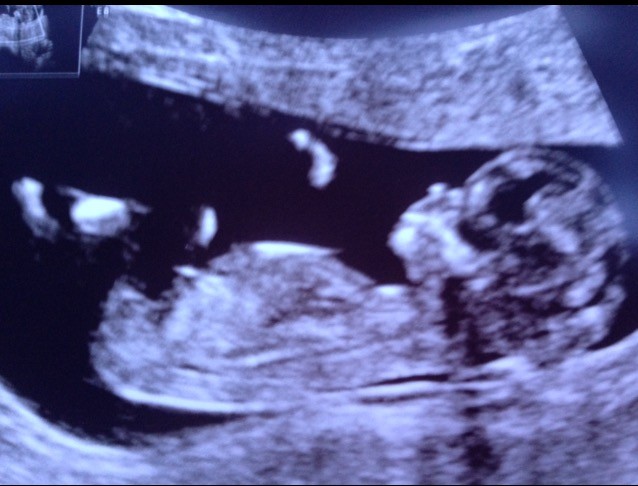

Suuuuper!Piękny,cudowny czlowieczekMówiłam że będzie dobrzeZobacz załącznik 834315 Jestem juz po badaniu. Dzieciaczek zdrowy, ma 6cmwyniki badan nifty byly ale nie chciala mi dr powiedziec jaka plec, powiedziala, ze nie badali tego.. tia jasne. Mowila, ze za 4tyg poznam juz plec na usg. Najwazniejsze, ze badania dobrze wyszly, plec nie ma znaczenia. Co do plamien to podobno tak sie zdarza i mam sie nie martwic, nie zbadala mi szyjki, bo to tez przy kolejnym usg, tsh tez do powtorzenia za 4tyg. Ach ta Dania..

Ale piękne fotoZobacz załącznik 834315 Jestem juz po badaniu. Dzieciaczek zdrowy, ma 6cmwyniki badan nifty byly ale nie chciala mi dr powiedziec jaka plec, powiedziala, ze nie badali tego.. tia jasne. Mowila, ze za 4tyg poznam juz plec na usg. Najwazniejsze, ze badania dobrze wyszly, plec nie ma znaczenia. Co do plamien to podobno tak sie zdarza i mam sie nie martwic, nie zbadala mi szyjki, bo to tez przy kolejnym usg, tsh tez do powtorzenia za 4tyg. Ach ta Dania..

Ale masz ślicznotę.Zobacz załącznik 834315 Jestem juz po badaniu. Dzieciaczek zdrowy, ma 6cmwyniki badan nifty byly ale nie chciala mi dr powiedziec jaka plec, powiedziala, ze nie badali tego.. tia jasne. Mowila, ze za 4tyg poznam juz plec na usg. Najwazniejsze, ze badania dobrze wyszly, plec nie ma znaczenia. Co do plamien to podobno tak sie zdarza i mam sie nie martwic, nie zbadala mi szyjki, bo to tez przy kolejnym usg, tsh tez do powtorzenia za 4tyg. Ach ta Dania..